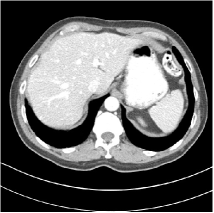

Refer to caption WavResNet [11]Refer to caption WavResNet [11]Refer to caption WavResNet [11]Refer to caption Momentum-Net (SimpleCNN)Refer to caption Momentum-Net (SimpleCNN)Refer to caption Momentum-Net (SimpleCNN)Refer to caption Momentum-Net (SimpleCNN-RSN)Refer to caption Momentum-Net (SimpleCNN-RSN)Refer to caption Momentum-Net (SimpleCNN-RSN)Refer to caption Momentum-Net (Dn-RSN)Refer to caption Momentum-Net (Dn-RSN)Refer to caption Momentum-Net (Dn-RSN)Refer to caption ReferenceRefer to caption ReferenceRefer to caption Reference

Fig. 3: Three examples (from top to bottom) of the reconstructed testing images using Momentum-Net with SimpleCNN (the second column), with SimpleCNN-RSN (the third column), and with Dn-RSN (the fourth column). The compared WavResNet denoised images are shown in the first column, and the reference images are in the fifth column. See their FBP images in Fig. 4.

Fig. 2 shows that the proposed Momentum-Net with SimpleCNN decreases RMSE dramatically in the first 30 layers, and tends to converge in 50 layers. The Momentum-Net reduces the mean RMSE value by 4.5 HU and gives smaller standard deviations in RMSE, compared to WavResNet, as reported in Table 1. This implies that the proposed Momentum-Net with SimpleCNN can improve both the accuracy and stability of low-dose CT image reconstruction than a state-of-the-art image denoising deep NN, WavResNet. The proposed Momentum-Net with SimpleCNN better removes noise and streak artifacts than WavResNet. It also provides clearer reconstructions of some details; see, in Fig. 3, the boundaries shown in the zoomed region at the top-right corner in the first example, the arrow pointed structures in zoomed areas of the second example, and the arrow pointed tissues in the left zoomed region in the third example.

We show the reconstructed examples by Momentum-Net with SimpleCNN-RSN and Dn-RSN in the third and fourth columns of Fig. 3 respectively. Comparing the first three and the last columns in Fig. 3, we observe that Momentum-Net with SimpleCNN-RSN provides generally noisier reconstructions than WavResNet and Momentum-Net with SimpleCNN. However, Momentum-Net with SimpleCNN-RSN sometimes can provide clearer details than WavResNet. For example, in the right zoomed box of the second example, Momentum-Net with SimpleCNN-RSN shows better reconstruction quality for the arrow pointed structures than WavResNet, and in the left zoomed box in the third row, the former gives clearer small tissues marked by red arrows than the latter. Table 1 reports that Momentum-Net with SimpleCNN-RSN is approximately 2.9 RMSE (HU) higher than WavResNet, while it has smaller standard deviations. This implies that Momentum-Net with SimpleCNN-RSN is more stable than WavResNet, although it may not provide better image qualities. Momentum-Net with Dn-RSN, however, provides the worst visual and numerical results among the compared four methods in this paper.